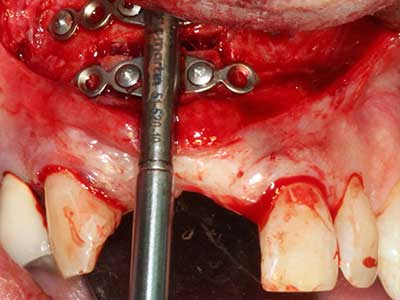

Wie sich in der Vergangenheit gezeigt hat stellt prinzipiell jeder knochenchirurgische Eingriff eine mögliche Indikation für die Piezochirurgie dar. So lässt sich die Präparation des mobilen Segmentes bei der Distraktionsosteogenese (Abb. 23-25) und der Sandwichosteotomie mit speziellen Ansätzen bewerkstelligen, ohne die für den Erfolg beider Techniken essenzielle Blutversorgung des krestalen Anteils zu gefährden (Gonzalez-Garcia, Diniz-Freitas et al. 2008).

Abb. 21: Ausgedehnter OK-Frontzahndefekt mit Indikation zur Distraktionsosteogenese bei vernarbtem Weichgewebe nach Vor-Operation.

Abb. 22: Das mobile Segment kann präzise mit der dünnen Osteotomiesäge (W&H Piezomed) separiert werden.

Abb. 23: Finale Mobilisation des palatinal gestielten Distraktionssegmentes mit dem Meissel.

Abb. 24: Anbringen des Distraktors (TRACK-System, KLS Martin).

Abb. 27: 21-jähriger Patient nach Umstellungsosteotomie mit persistierender Retrognathie bei Klasse II-Dysgnathie.

Abb. 28: Im Rahmen der Metallentfernung erfolgt die Abtrennung der basalen Kinnanteile unter Beibehaltung der lingualen Blutversorgung mit dem Piezomed.

Abb. 29: Vorverlagerung des Kinns um 5 mm und Fixierung mittels zweier Osteosyntheseplatten (KLS Martin). Im Randbereich sind beide Nn. mentalii zu erkennen.